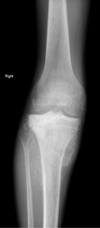

2

3